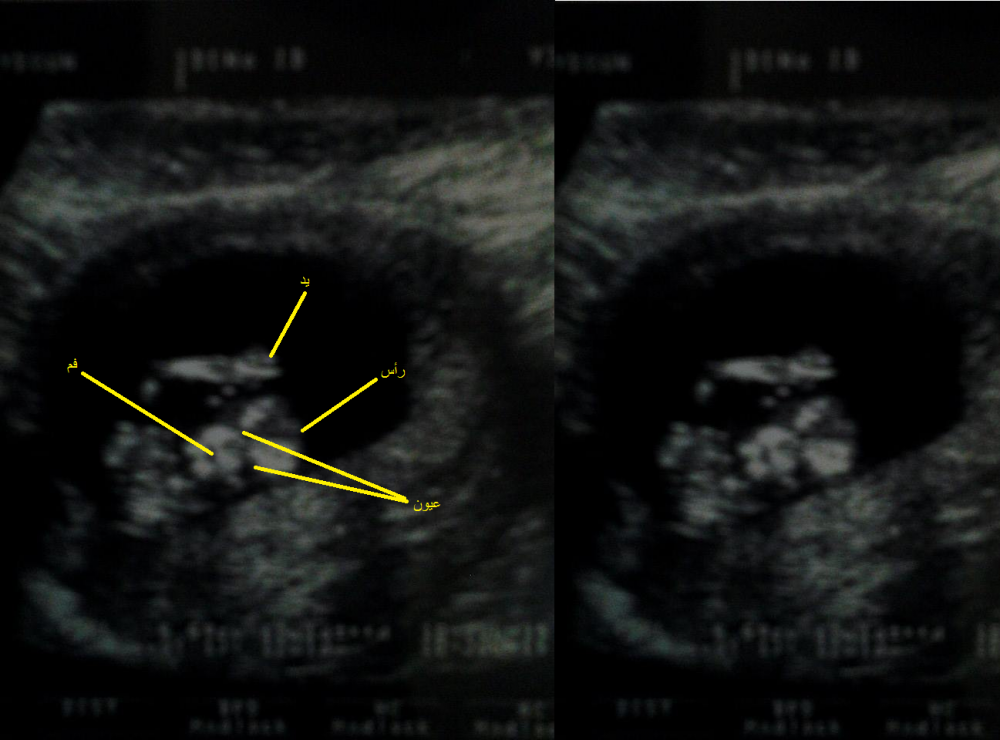

وعملتلي الترا ساوند للبيبي وكان كل ما تحاول تحركو يرفع ايدو ويعمل سلااام بايدو،، صارت تحكي شكلو بيبي خلوق بيضل يرد السلام ههههه

وهدول هم الصور بصورة بسلم عليكم،، وبصورة جاعص وحاطط ايدو تحت راسو